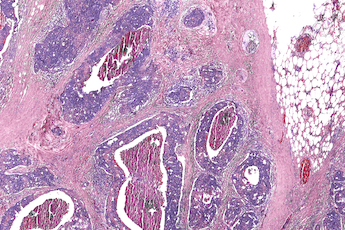

In trials, the group assessed healthy and cancerous breast cancer tissues, comparing the results of the hybrid microscope's computed dyes with those from conventional staining technique. The digital biopsy closely correlated with the traditional one, according to UICU.

In its published paper, the group commented that the IR-OH system demonstrated a four-fold increase in spatial resolution compared to conventional IR microscopy, along with an improvement in spectral consistency due to its mitigation of scattering effects.

"The combined impact of these advances allows full-slide infrared absorption images of unstained breast tissue sections on a visible microscope platform," noted the team. "We show that automated histopathologic segmentation and generation of computationally stained images is possible, resolving morphological features in both color and spatial detail comparable to current pathology protocols but without stains or human interpretation."